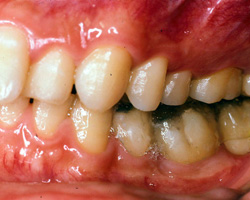

今回、この患者様のスプリント調整は、装着時から三回までは一週間ごと、四回から七回までは三週間ことのを三カ月かけて調整。その後、スプリントを再製作し装着、以降三カ月に一度の調整を二年間線り返しました。写真3) 4) 5) 6)はその時の状態です。臼歯部が大きく離閉じているのがおわかりかと思いますが、この隙間が頭蓋骨の歪み、頚椎の歪みが咬合面上に現れた状態で、決して歯牙が歯槽骨内に埋入したわけではありません。

| 写真5)2年後の状態(左側) | 写真6)スプリントをはずした時の状態(左側) |